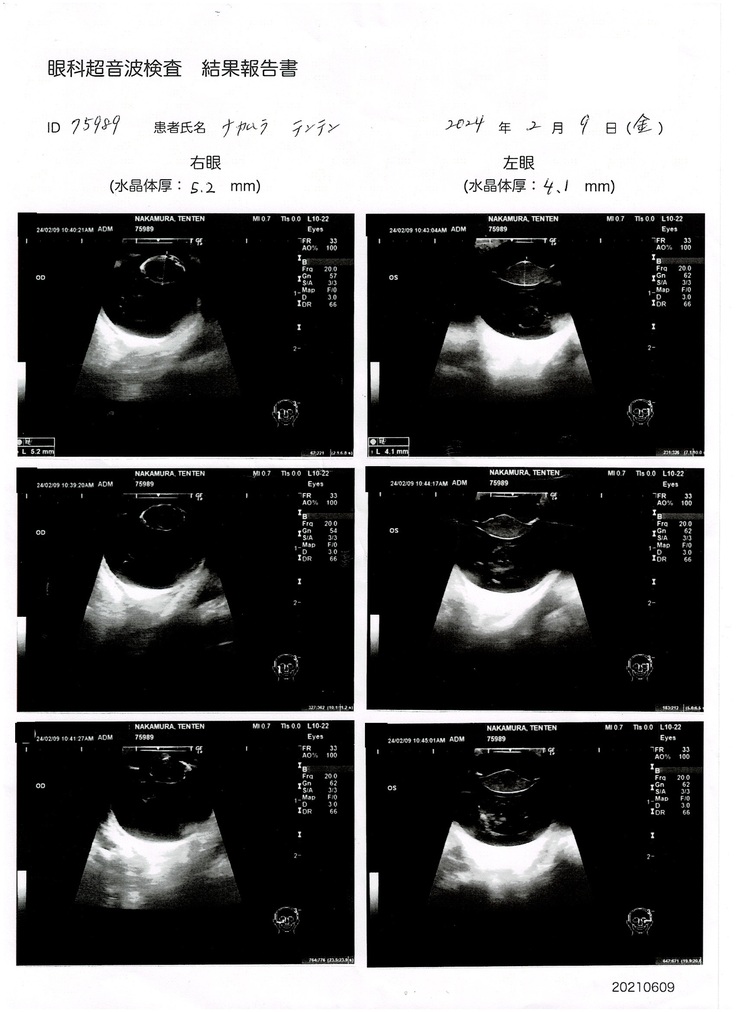

【2024年2月9日】

手術をするために必要な網膜電位図(ERG)検査、眼科超音波検査を受けました。